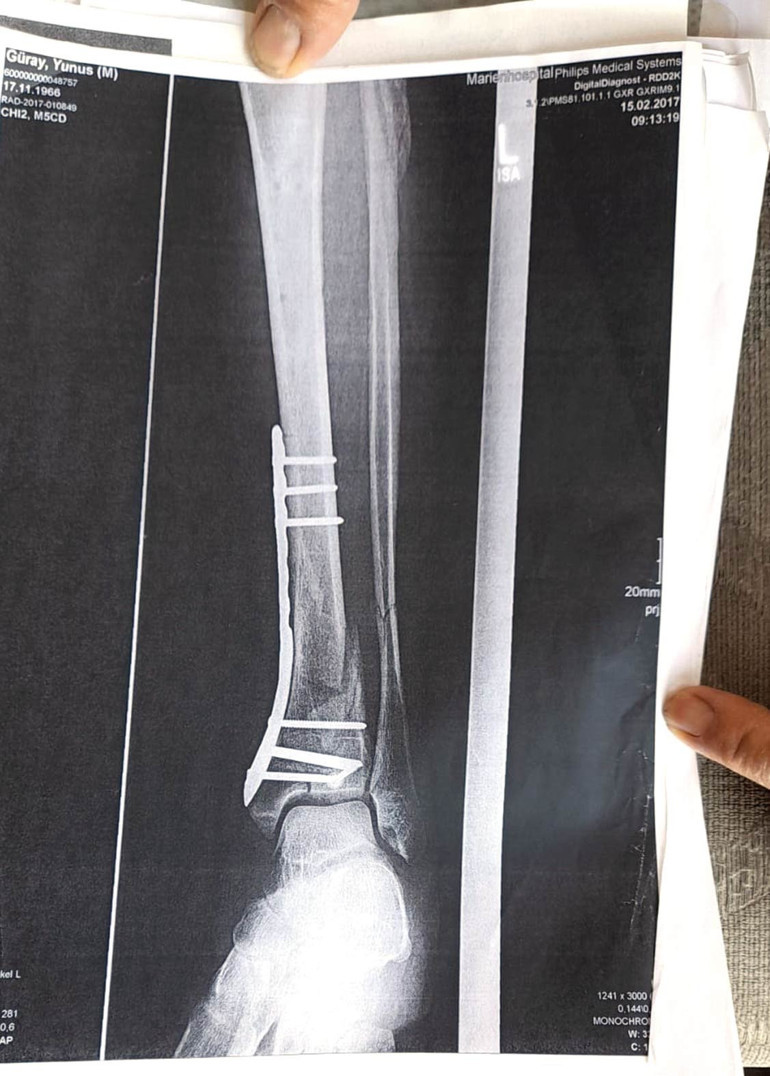

Olay gününü anlatan Yunus Güray, “Yılbaşı günüydü, havaalanına indik. O gün 3-5 kişi vardı. Bir taksi tuttuk beraber. Şehir içine eğlenerek geldik. Otele yerleştim ve ‘Yılbaşını burada nasıl kutluyorlar bakayım’ dedim. Geleli daha 1-2 saat olmuştu. Yat Limanı’na doğru indim. Asansör var sol tarafta, kafeler vardı önceden yeşil alandı. Orada ateş yakmışlar. Dans ediyorlardı, kapalı bir yer vardı. ‘Karşıya geçeyim, ateşe bakayım’ dedim. Merdivenler vardı 50 metre ileride. Çukurları görmedim, yürürken 2 metre aşağı düştüm tek ayağım üzerine. Ayağımı topuk, oynak yerinden kırdım. Etrafı koruma altında değildi. 1 hafta sonra özel uçakla Almanya’ya döndüm. Ömrümü yediler, demir var ayağımda, sakat bıraktılar. Ayağı keseceklerdi neredeyse. Şu an kalıcı sakatlık var. 1 sene kendime gelemedim, 2 haftada bir ameliyata giriyordum. Almanya’da 3 ay hastanede kaldım ve ayağımda yüzde 3’lük engel oluştu. Benim uçak masrafım sadece 22 bin Euro tuttu. 9 yıl oldu, bir tane çukur değildi. Adamlar kazmış, kazmış, bırakmış. Tam merkezde bu olay, hani ormanda bir yerde olur, ‘Tamam benim de hatam var. Gittim de düştüm’ derim. Ama şehrin merkezinde, etrafı çevrili değildi. Yemyeşil alan, gece vaktiydi. Ben mahkemeye verdim, o çukurları 3 ay sonra kapattılar. Adil bir karar olmadı,” dedi.

Yunus Güray’ın ayağında yüzde 3’lük engel oluştu.